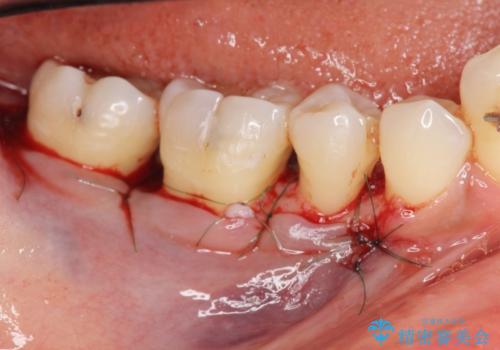

歯を抜かずに残せるよう、再生療法・歯周ポケット除去手術を計画します。

再生治療を行うことで、吸収した骨を再生し歯を保存できることがあります。